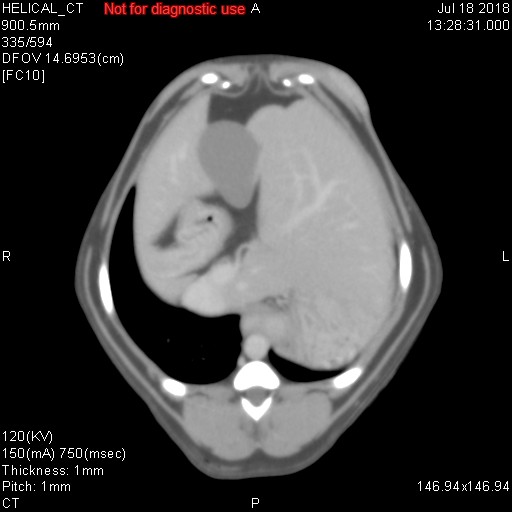

上記に載せました各写真ですが、CT検査で様々な条件で撮影した同一臓器(肝臓/胆嚢/胃/十二指腸/門脈/後大静脈/大動脈/肝動脈)です。CT検査では、そのまま撮影するプレーン、造影剤を使用する動脈相・門脈相・平行相がありますが、上記写真がどれかわかりますでしょうか??

シンプルに、一番上がプレーンです。臓器のシルエットくらいしかわかりません。その次が動脈相で、中央にピョろっとある肝動脈や背骨側にある太い血管(大動脈)が白くはっきりと写ります。また薄っすらと肝臓内にも多くの動脈がありますので、チラチラと動脈だけが見えてきます。3番目が門脈相といって肝臓の外にある門脈が白く際立ち、さらには肝臓内にある門脈(門脈枝)まで白くキレイに写ってきます。そして最後が平行相ですが、これは造影剤が通過して結構時間が経過した際の写真ですが、例えば具合が悪い臓器だと造影剤が抜けきるのが遅いため、時間が経過しているにもかかわらず造影剤がまだ残ってしまったりしますので、そのような際の評価に活かされます(あと悪性腫瘍など癌なども同じような見え方をします)。

造影剤を投与したあと20秒経過したときに撮影するのが動脈相、40秒が門脈相、120秒が平衡相といい、時間経過でCTスキャンを行って、様々な条件のもとで画像は分析されていきます。あと細かいですが、とある数字を設定して、その数字に達したらCTスキャンが開始されるなど、撮影方法にもいろいろあります。ただ単純にCTスキャンをしているだけではなく、造影剤を使用したり、投与時間を細かく設定したり、さらにいろいろな条件下で画像を比較して、最適かつ確実な画像診断を行っているのが、CT検査なのです。